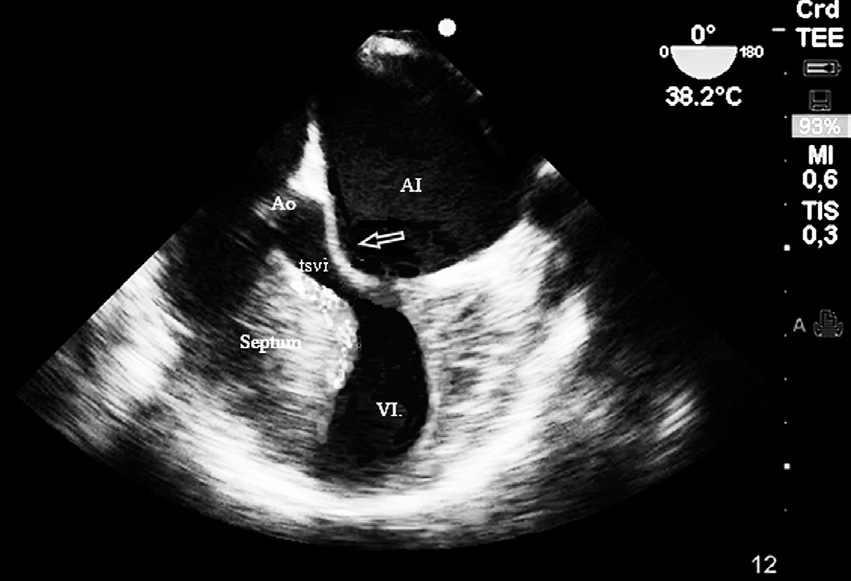

Al ingreso al pabellón quirúrgico se monitoriza con oximetría de pulso, presión arterial invasiva y electrocardiografía continua de tres derivaciones, que mostraban una frecuencia cardiaca normal. Se colocó un catéter epidural lumbar G18 en el espacio L2-L3 para proporcionar analgesia postoperatoria y se induce anestesia general endovenosa en modo TCI (target-controlled infusión) con propofol y remifentanil, para una concentración sitio efecto de 2,6 ug ml-1 y 4,5 ng ml-1, respectivamente, como relajante muscular se utilizó rocuronio 0,6 mg kg-1. Inmediatamente de realizada la intubación endotraqueal se instaló un transductor multiplanar (3-8 Mhz) de ecocardiografía transesofágica (FujiFilm Sonosite Edge®) para monitorización intraoperatoria, obteniéndose mediciones basales de fracción de eyección y de precarga, la primera en un plano medio esofágico, visión de cuatro cámaras con método de Simpson, constatándose una fracción de eyección de 55% y la segunda en una visión transgástrica profunda en un eje corto midiendo el área de fin de diástole del ventrículo izquierdo como indicador del volumen de fin de diástole , siendo este de 9 cm2 (valor normal: 8-14 cm2) Durante la cirugía se mantuvo una vigilancia continua del tracto de salida del ventrículo izquierdo (TSVI) a través de la visión de cuatro cámaras a 0º y 130º para la detección precoz de SAM (Figura 1). El desarrollo de la cirugía transcurrió sin incidentes hasta el momento del alumbramiento. Luego de la administración de oxitocina endovenosa (syntocinon®) 2 UI, presentó hipotensión sistólica de 65 mm Hg con una frecuencia cardiaca de 125 latidos por minuto. Las imágenes ecocardiográficas en el eje corto intragástrico mostraban una disminución del área de fin de diástole del ventrículo izquierdo de menos de 8 cm2 y en el plano medio esofágico visión de cuatro cámaras una disminución cualitativa del diámetro del TSVI en base al desplazamiento del velo anterior de la válvula mitral sin obstrucción total (Figura 2). El doppler color de la válvula mitral mostraba un jet sistólico de regurgitación que abarcaba dos tercios de la aurícula izquierda. En base a estas imágenes se determinó administrar bolos de cristaloides de 100 ml para mantener un área de fin de diástole ventricular mayor de 10 cm2. Como la frecuencia cardiaca permaneció elevada se inició bloqueo beta mimético con propanolol, en bolos de 0,5 mg hasta un total de 1,5 mg endovenoso, obteniéndose con estas medidas estabilidad hemodinámica. En las imágenes ecocardiográficas se observó nuevamente un normal desplazamiento del velo anterior de la válvula mitral.

Figura 2 Imagen ecocardiográfica 4 Cámaras 0º, que muestra la obstrucción dinámica del tracto de salida ventrículo izquierdo (TSVI) en sístole. La fecha muestra el velo anterior de la válvula mitral.